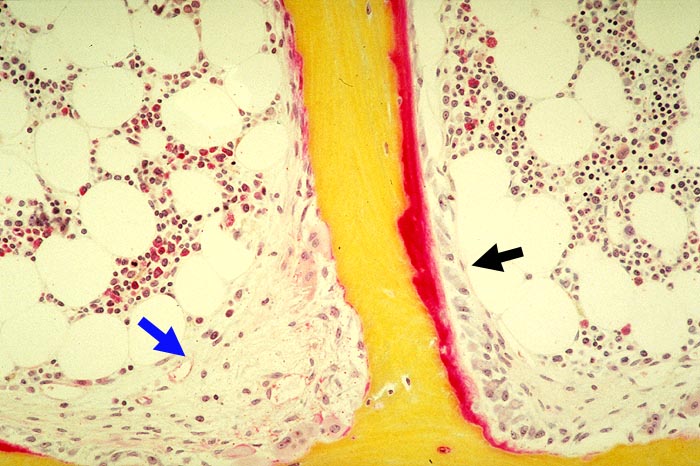

Renale Osteopathie

Knochen, Knorpel, Gelenke

Knochen

Knochen (Wirbelkörper und Discus intervertebralis)

Pathologischer Befund